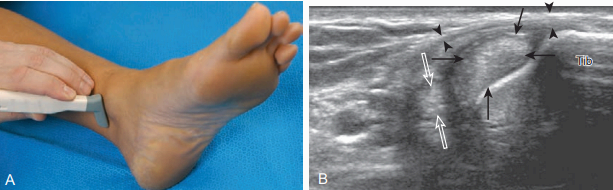

안쪽 발목 검사 발목의 안쪽을 검사하기 위해서는 누워있는 환자의 발을 바깥돌림하여 발목의 안쪽면을 잘 검사할 수 있도록 한다. 먼저 안쪽복사보다 위쪽에서 가로면 검사부터 시작한다. 정강뼈 표면의 높은 에코가 확인되면 탐촉자를 뒤쪽으로 이동시킨다. 가로면 영상에서 첫 번째 보이는 힘줄은 뒤정강힘줄이며, 탐촉자의 각도를 약간씩 조절하면 주변 지방조직의 높은 에코와 구별되는 힘줄을 볼 수 있다. 그 후 탐촉자를 약간씩 뒤로 이동시키면 긴 발가락굽힘힘줄, 뒤정강 동맥과 정맥, 정강신경, 긴 엄지굽힘힘줄을 순서대로 확인할 수 있다.